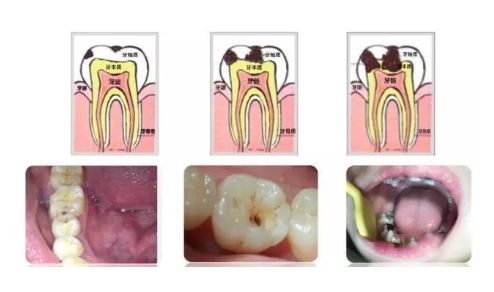

龋齿的形成是一个相对较缓慢的过程。根据龋齿的深度,我们分为三个不同的阶段,浅龋、中龋和深龋。不同的阶段有不同的症状。

当牙釉质持续的破坏腐蚀后,就会慢慢形成浅表的破坏。浅龋可能是黑色的窝沟或者很小的龋洞,也可以仅仅表现为白色的斑块。这个时候因为牙齿破坏小并且没有明显的症状往往很难引起人们的注意。然后龋洞逐渐扩大,进入到牙本质形成较大的龋洞,这时食物会卡在洞里面,有可能吃点甜食就会酸痛。再往下发展达到牙本质深层形成深龋时,症状就更明显了,冷热刺激时都会感到疼痛。像图中这颗牙破坏的范围很广,整个牙齿表面都变黑了。